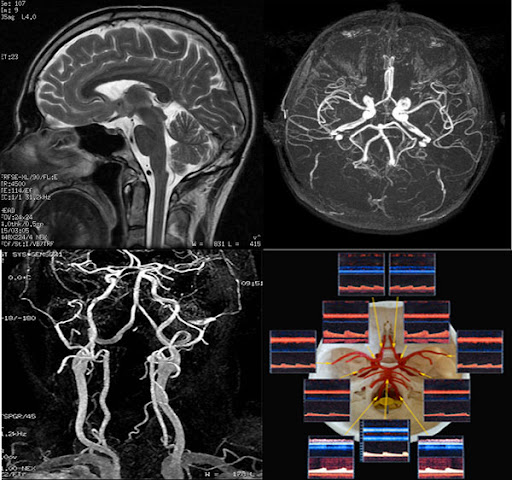

MRI(자기 공명 영상)은 강력한 자기장과 라디오파를 이용하여 체내 조직의 이미지를 생성하는 기술입니다. MRI는 연부 조직, 즉 뇌, spinal cord, 근육, 그리고 다양한 내장 장기 등을 상세하게 볼 수 있는 특징이 있습니다. 주로 신경계, 근골격계 및 종양 연구의 진단 도구로 사용됩니다.

반면에 MRA(자기 공명 혈관 영상)는 MRI의 일종으로, 혈관의 이미지를 생성하는 데 초점을 맞추고 있습니다. 이는 혈관의 구조 및 흐름을 평가하는 데 유용하며, 주로 심혈관 질환의 진단에 사용됩니다. MRA는 특히 혈관의 협착이나 막힘, 동맥류와 같은 혈관 관련 문제를 발견하는 데 매우 유용합니다.

MRI는 인체 내의 수소 원자의 자기적 성질을 이용하여 이미지를 생성합니다. 강력한 자기장이 수소 원자를 정렬시킨 후, 라디오 파를 통해 이들을 자극하여 방출되는 신호를 수집합니다. 수집된 신호는 컴퓨터에 의해 해석되어 이미지를 만들어 내는데, 이 과정에서 세부적인 이미지가 생성되어 체내 구조를 명확하게 볼 수 있게 됩니다.

MRA는 MRI의 기법을 기반으로 하므로, 기본적으로는 동일한 작동 원리를 가지고 있지만, 약간의 차이점이 있습니다. MRA는 특히 혈관을 시각화하는 데 최적화되어 있으며, 주로 조영제를 사용하여 혈관을 더욱 뚜렷하게 구분합니다. 조영제는 혈관 내에서 신호의 차이를 만들어 신호 강도를 높여줍니다. 이로 인해 혈관의 형태와 상태를 더욱 명확하게 시각화할 수 있습니다.